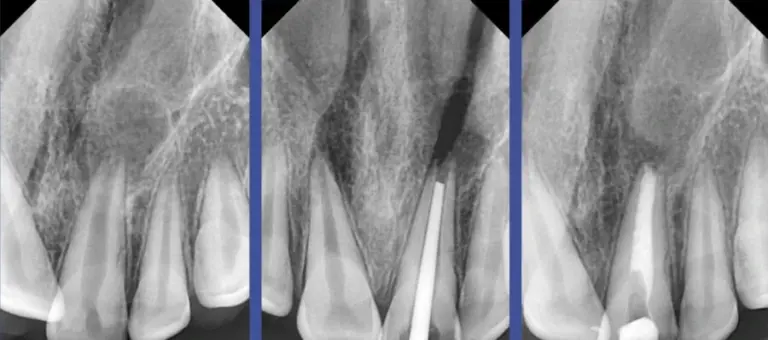

Đọc tiếpPhân tích các hình ảnh X quang của bệnh lý nội nha là một phần không thể thiếu trong chẩn…